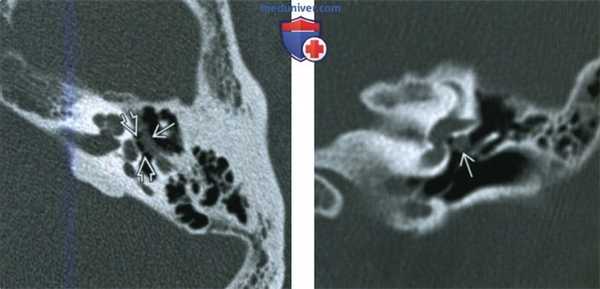

(Слева) При корональной КТ левой височной кости определяется нормальный барабанный сегмент лицевого нерва (поперечный срез) рядом с нижней поверхностью латерального полукружного канала. Обратите внимание на едва заметную костную стенку канала; оцените отношение к нише овального окна.

(Справа) При корональной КТ левой височной кости визуализируется очаговое объемное образование, исходящее из средней части барабанного сегмента лицевого нерва. Образование - выбухающий лицевой нерв, не шваннома. Выбухание лицевого нерва может приводить к значительным сложностям при стапедэктомии.

(Слева) При аксиальной КТ в костном окне у этого же пациента определяется протрузия барабанного сегмента ЧН VII в виде «гамака», натянутого в полости среднего уха. Обратите внимание на ЧН VII, достигающего ножки стремечка, что объясняет кондуктивную тугоухость.

(Справа) При корональной КТ левой височной кости визуализируется округлая мягкотканная структура, выбухающая из среднего барабанного сегмента ЧH VII. МРТ С+ позволяет различить протру-зию ЧH VII (не контрастируем) и шванному лицевого нерва (контрастируем).